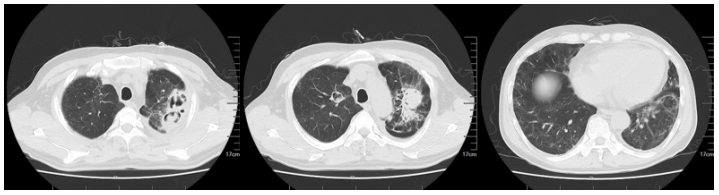

现病史:患者2024年1月7日左右无明显诱因下出现鼻塞等,外院胸部CT示:两肺炎症,肝内多发低密度灶。1月18日胸部CT:两肺散在渗出、斑点及空洞(图11)。当地医院予哌拉西林他唑巴坦抗感染,1月20日住院期间发热,热峰37.6℃,1月23日发热,热峰39℃,更换抗生素为头孢哌酮舒巴坦+左氧氟沙星,患者仍反复发热,1月25日达热峰38.4℃。

图片

图11  患者胸部CT(2024-01-18)

1月31日复查胸部CT提示病灶进展,出现团块及空洞样改变(图12)

图12  患者复查胸部CT(2024-01-31)

2月9日再次复查胸部CT可见肺部弥漫及多发病灶较前吸收(图13)。患者症状改善,体温恢复正常,遂予出院,序贯艾沙康唑胶囊200 mg qd。

图13  患者复查胸部CT(2024-02-09)